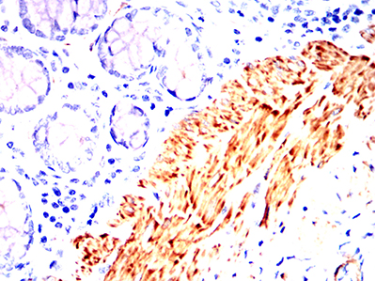

| AC1029 | ACTA2 Mouse Monoclonal antibody[1H8B8] | 100ug | $367 | 10days |

| AC1029 | ACTA2 Mouse Monoclonal antibody[1H8B8] | 200ug | $660.6 | 10days |